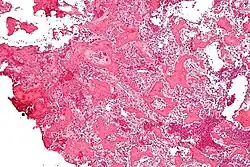

Micrograph of an osteoid osteoma showing the characteristic anastomosing bony trabeculae and osteoblastic rimming. H&E stain.

On histological examination, osteoid osteoma consists of a small (< 1.5–2 cm), yellowish-to-red nidus of osteoid and woven bone with interconnected trabeculae, and a background and rim of highly vascularized, fibrous connective tissue. Varying degrees of sclerotic bone reaction may surround the lesion. Benign osteoblastoma is virtually indistinguishable from osteoid osteoma. The usual appearance included a fibrovascular stroma with numerous osteoblasts, osteoid tissue, well-formed woven bone, and giant cells. The osteoblasts were generally small and regular in shape.[7]